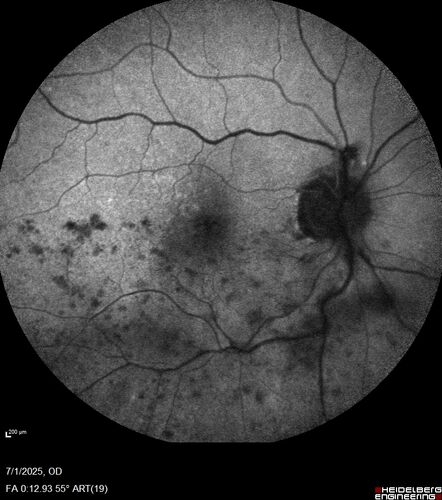

Hemi-CRVO - dual trunk vein

81 year old female mild vision loss - Anatomy shows dual trunk vein with one blocked. About 20 percent of people have this anatomy